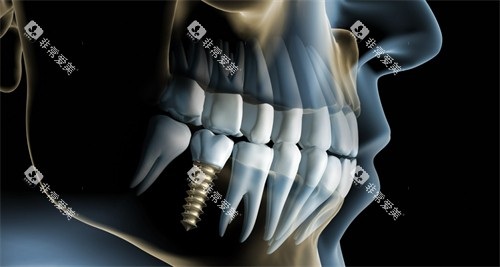

国产种植牙:5520元至15230元左右/颗。

韩国登腾种植牙:5500元至7000元不等/颗。

韩国奥齿泰种植牙:7000元至9800元不等/颗。

美国百康种植体:9000元至13000元不等/颗。

美国皓圣种植牙:6000元至10000元不等/颗。

德国Camlog种植牙:10000元起/颗。

瑞典诺贝尔种植牙:9800元至12000元不等/颗。

瑞士ITI种植牙:12000元至20000元不等/颗

瑞士ITI亲水种植牙:14800元起/颗。

半口种植牙:3万元至20万元不等。

全口种植牙:6万元至40万元不等。

上门牙即刻种植:8180元至9492元。